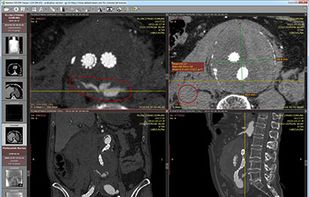

DICOM viewer. RadiAnt is a DICOM viewer for medical images designed to provide you with a unique experience. With its intuitive interface and unrivaled performance, you'll never look back.